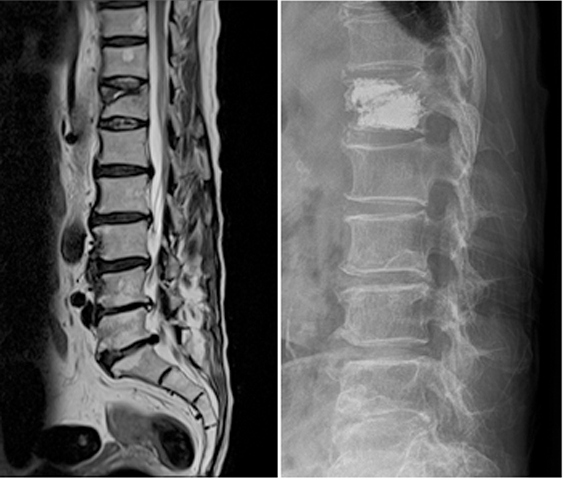

1.척추분리증으로 인한 척추전방전위증 환자의 수술전 사진

2.인공 디스크와 나사못을 이용한 척추유합술 및 후방 나사못 고정술로 척추분리증과 척추전방전위증이 교정된 상태